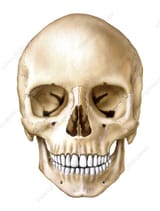

How much does your face change in your 20s?

Looking at pictures of myself when I was 19 (29 now) and my skull got FUCKED up. It's much wider and my brow ridge got really pronounced. I never did TRT or anything like that. I look like a caveman now :(